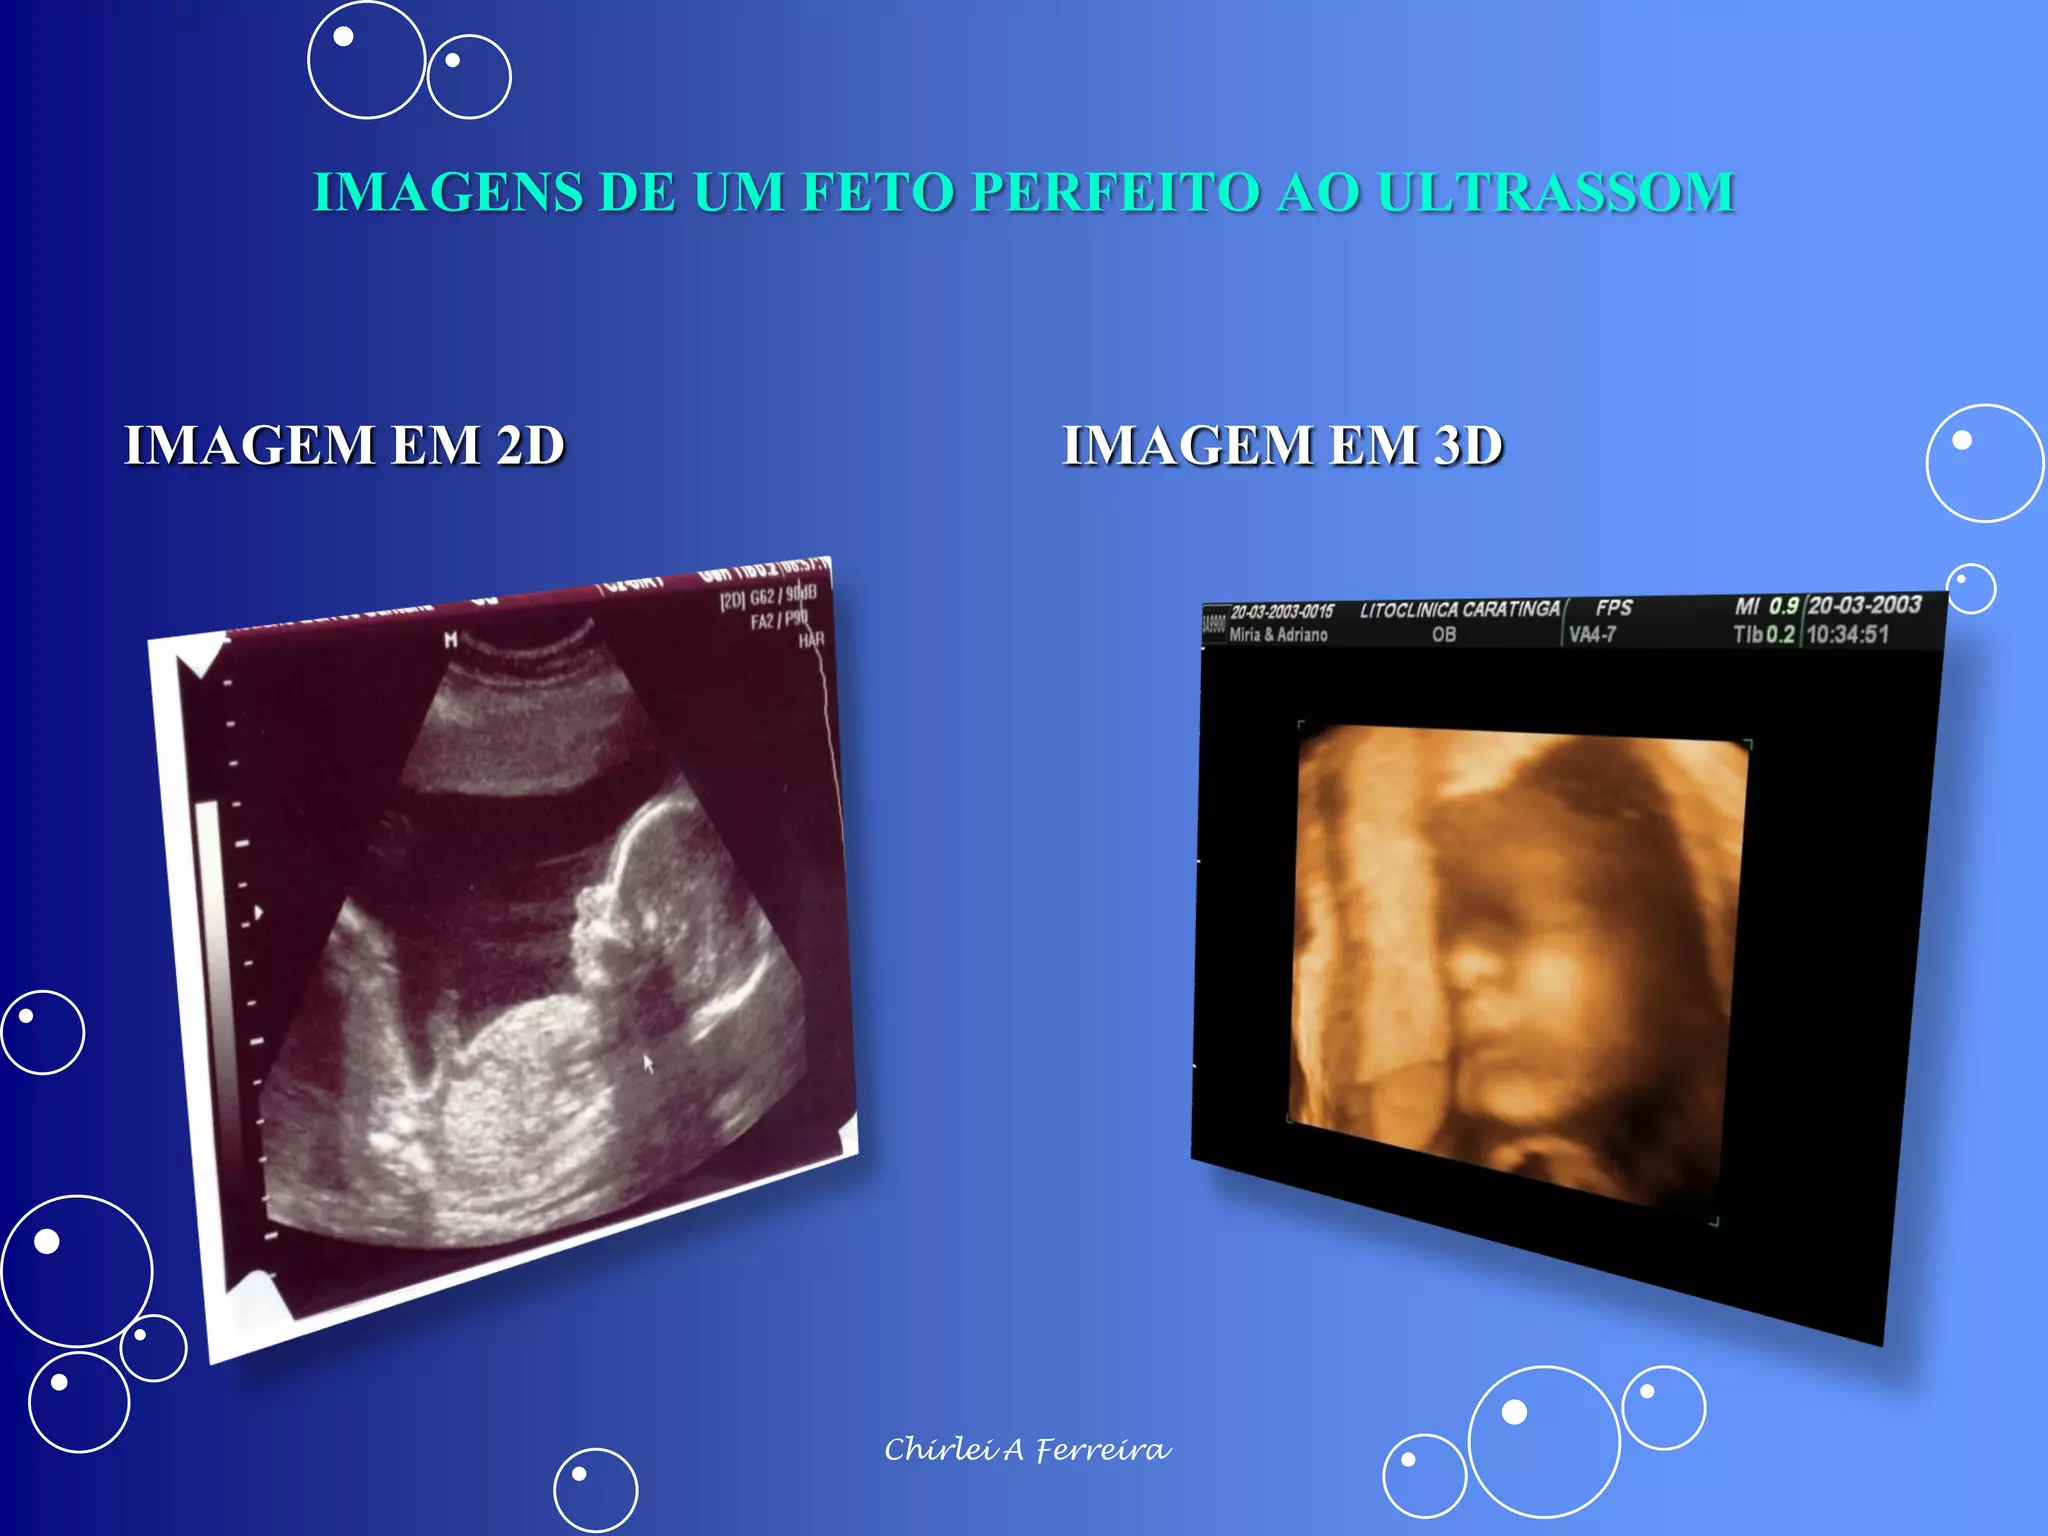

O documento discute as alterações fisiológicas da gravidez, incluindo mudanças no corpo da mulher, como aumento do tamanho do útero, variações nas mamas e modificações no sistema circulatório e respiratório. Também aborda as adaptações nos órgãos pélvicos e as consequências para a saúde, como o surgimento de estrias e varizes. Além disso, menciona a importância do ultrassom para a visualização do feto e avaliação do crescimento fetal.